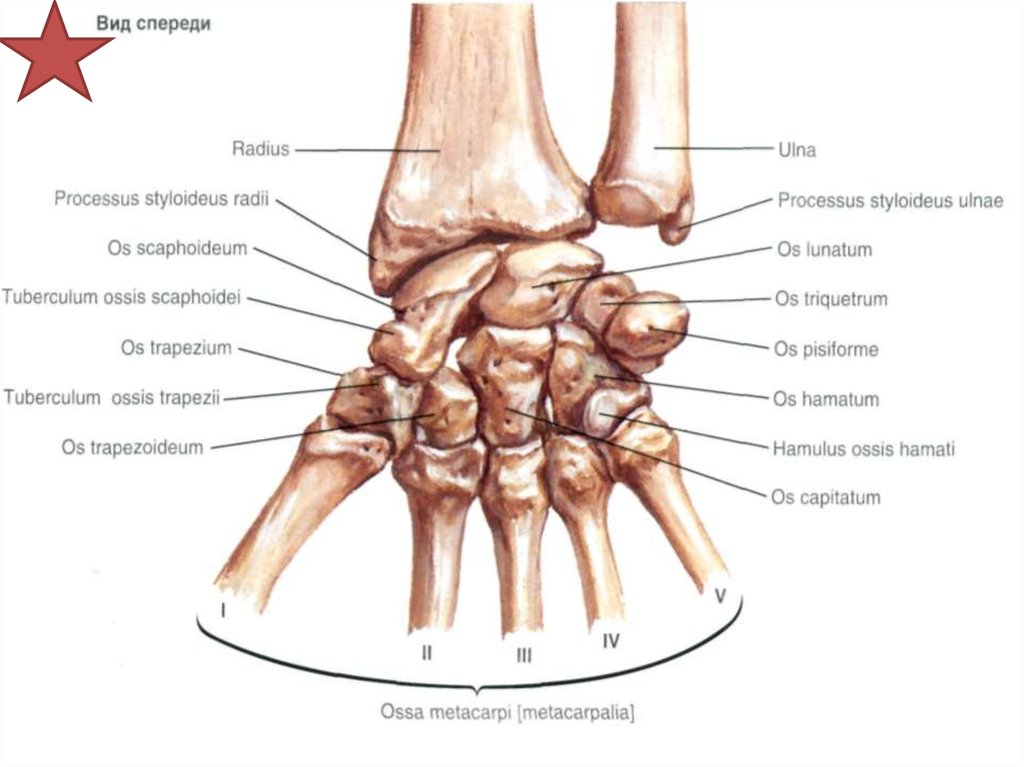

Анатомия кисти руки и строение костей